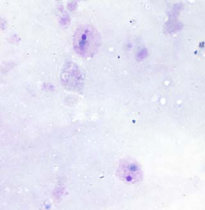

گامتوسیت

گامتوسیت‌های پلاسمودیوم ویواکس گرد تا بیضی شکل، با رنگدانه‌های پراکنده‌ی قهوه‌ای می‌باشند و می‌توانند تمام گلبول قرمز را پر کنند. نقاط شوفنر در این گونه، ظریف‌تر از پلاسمودیوم اُوالی ظاهر می‌شوند.

گامتوسیت در اسمیرهای خونی نازک

یک جفت گامتوسیت در اسمیر خونی نازک

به بزرگ شدگی گلبول‌های قرمز آلوده و پراکنده بودن رنگدانه‌ها دقت کنید.